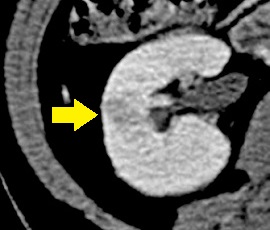

CT画像